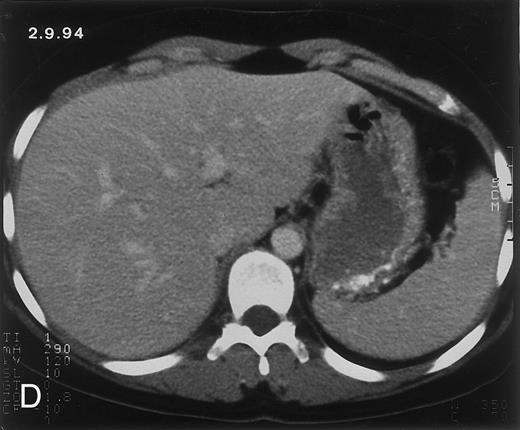

(D) On August 23, 15 days after the neutrophil count had dropped below 500/μL in the third chemotherapy cycle, focal liver lesions clearly decreased in size and number. (E) On September 30, 35 days after neutrophil recovery, multiple hepatic abscesses are seen (arrowhead). To show maximal extent of lesions the scan shown is at a slightly different level. (F) On June 16, 1994, 230 days after neutrophil recovery, the CT scan has normalized.

Radiologic evolution in patient A. (A) Postcontrast abdominal CT scan on March 16, 1993 shows multiple small hypodense areas in all segments of the liver, suggestive of hepatic candidiasis. Seven days previously, the patient had recovered from severe neutropenia after the first cycle of chemotherapy for AML. (B) On April 23, 6 days after the neutrophil count had dropped below 500/μL in the second cycle of chemotherapy, there is no evidence of focal lesions on postcontrast CT scan. (C) On June 18, when neutrophils were normalized for 46 days, CT scan again shows multiple small abscesses.

Evolution of fungal lesions on CT scans during and after neutropenia is summarized in Table 2. Figure 1 (patient A) and Fig 2 (patient B) serve to illustrate Table 2.

In three patients, multiple round lesions were seen on postcontrast CT scans of the abdomen in the liver and the spleen, while in two cases, lesions could only be seen in the liver (Table 2). Following the diagnosis of disseminated candidiasis, these lesions decreased in size and visibility during subsequent neutropenia in three patients (compare Fig 2A and B) and disappeared completely in two patients (compare Fig 1A and B). The numbers of days of severe neutropenia (neutrophils <500/μL) at the time the CT scan was performed are listed in Table 2. After recovery from neutropenia and despite continued antifungal therapy, the size and visibility of the lesions increased again (Fig 1C). Similarly, the number of days since recovery from severe neutropenia (neutrophils >500/μL) are listed in Table 2. In two of three patients treated with another cycle of myeloablative chemotherapy, this waxing and waning pattern of radiologic lesions could be seen again (Fig 1D and E). In all patients, lesions eventually disappeared (Figs 1F and 2D) after prolonged antifungal therapy.